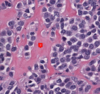

psomma body

papillary carcinoma

Psammoma body: calcified structures (tumor cell necrosis)